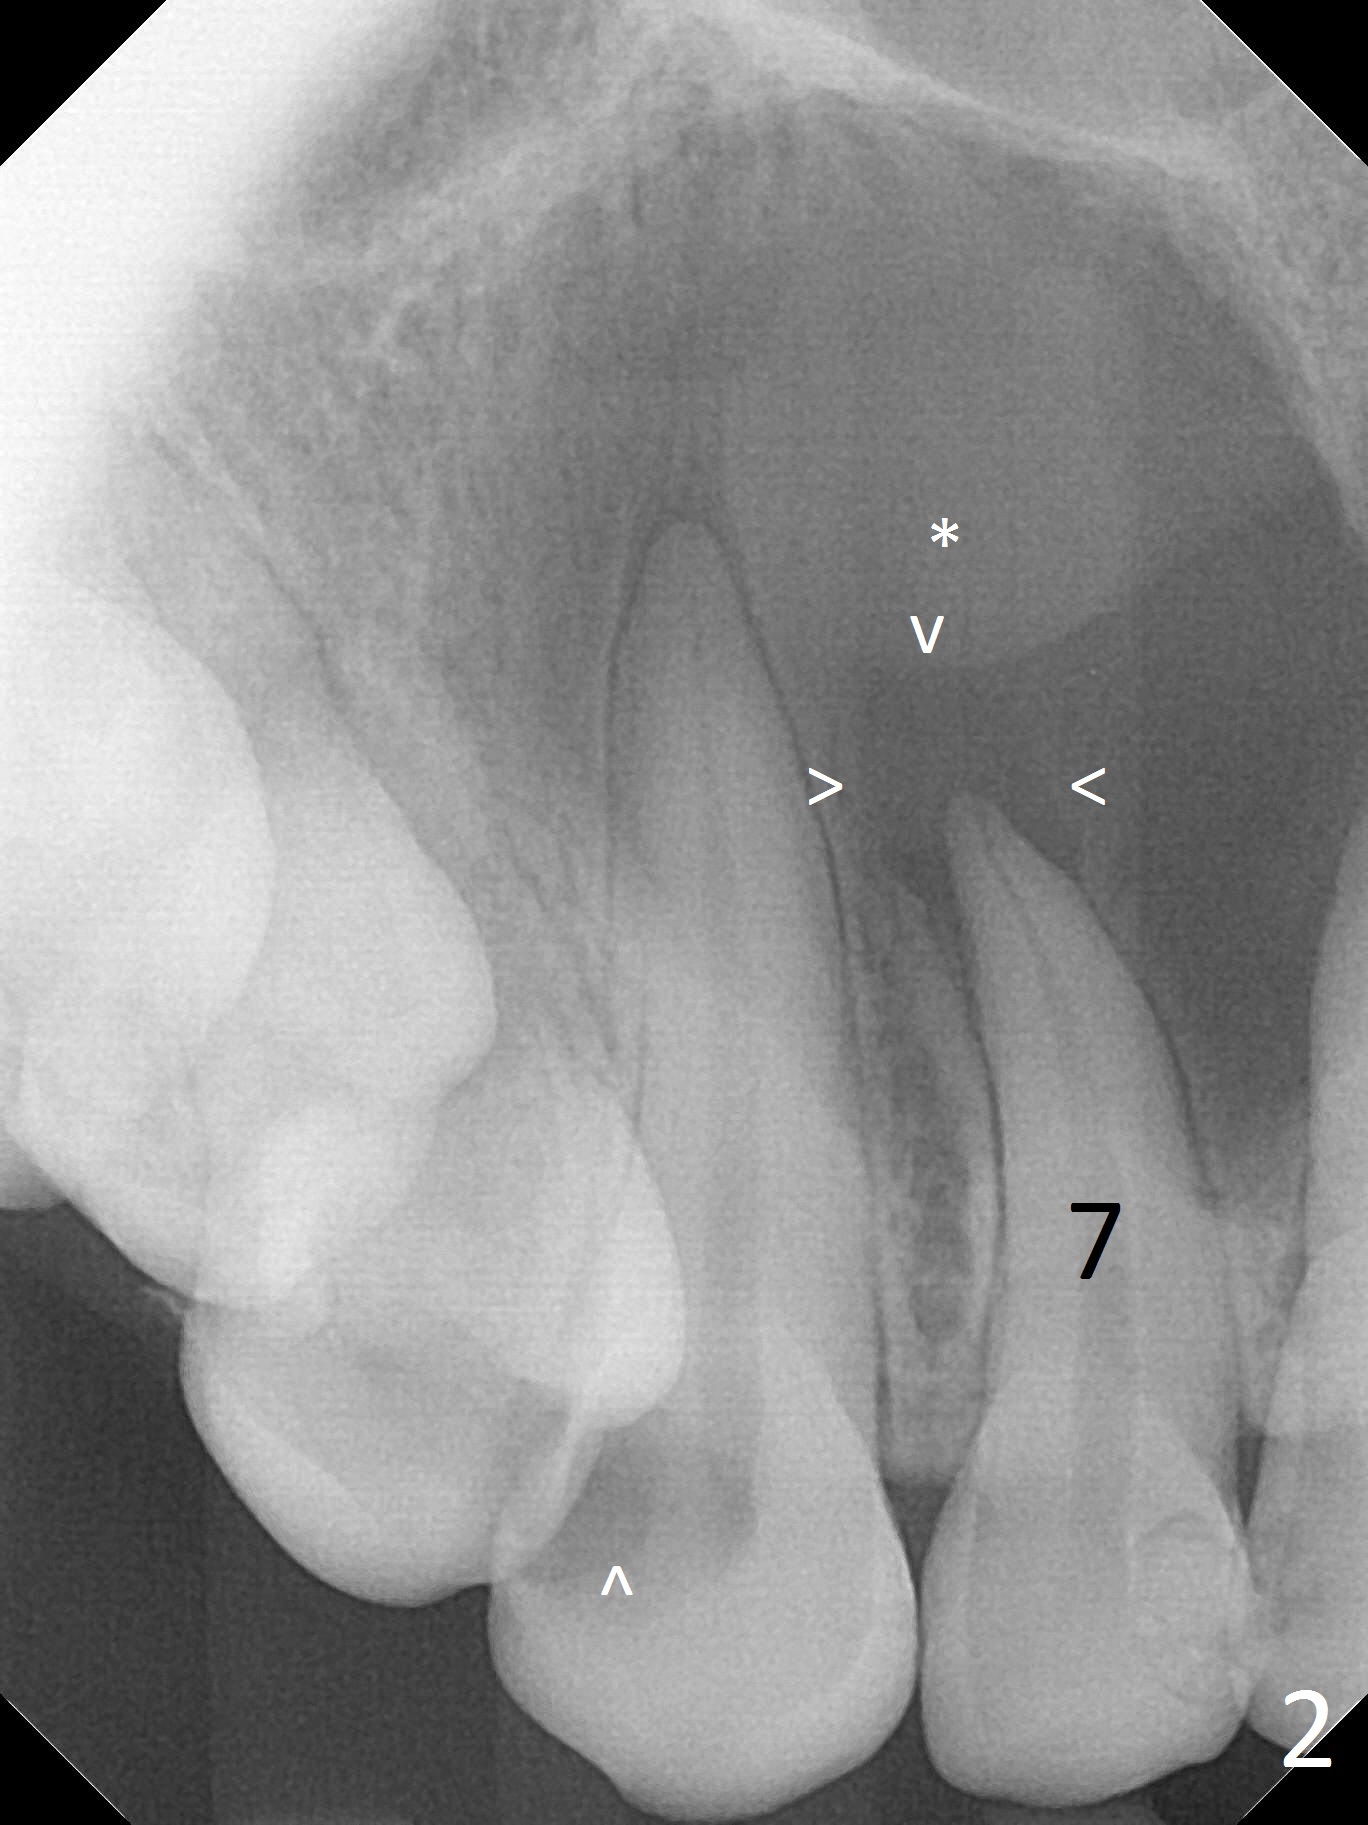

When this patient returns with improvement of symptoms, RCT will be finished. In fact the swelling relapses a month later (Fig.6). After discussion of possible cyst enucleation and increase in debridement from 30/.04 to 40/.06, a master cone of 40/.06 is inserted (Fig.7) and RCT is finished (Fig.8). Although the patient reports relapse of swelling, the palate looks normal and bone density increases 7 months postop (Fig.9). For 14 implant placement, CT is taken 2 years 1 month post RCT (Fig.10,11). Radiolucency is confined to the apex of the tooth #7 (white *). The labial concavities mesial and distal to the left lateral incisor makes radiolucencies (bone loss) look more radiolucent, creating globumaxillary cyst image. The globumaxillary cyst is a terminology for its shape. It does not mean congenital in nature. The treatment is dependent upon vitality test of the involved teeth.